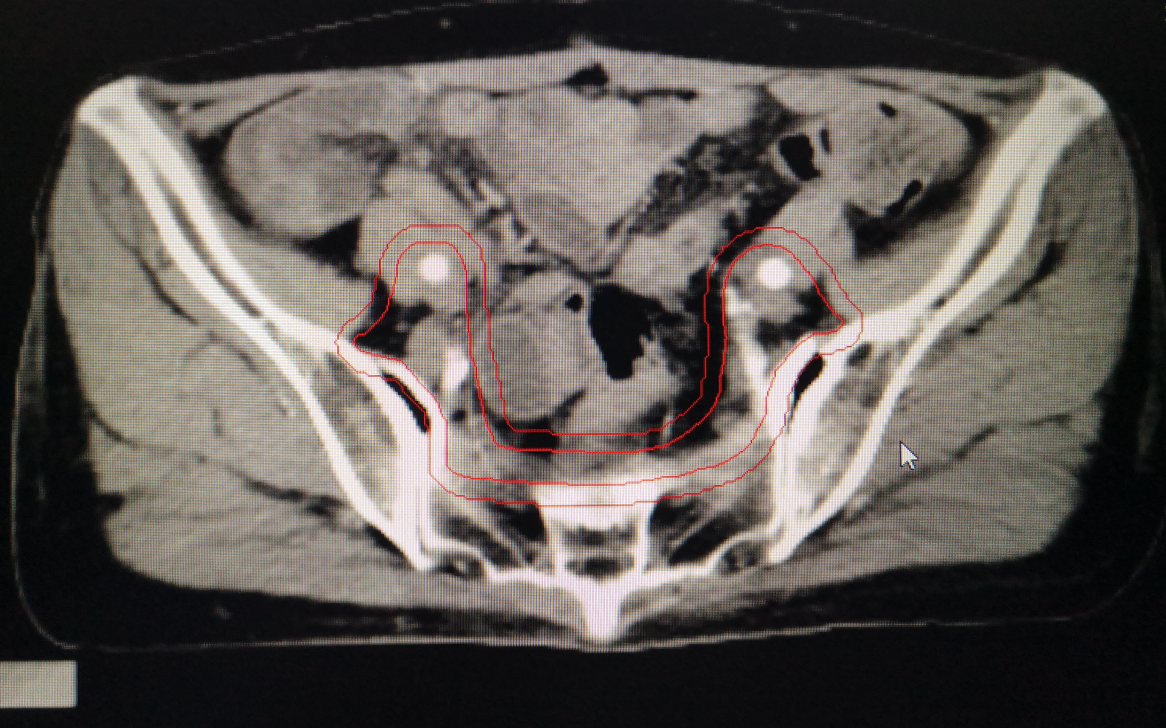

婦科腫瘤術後勾畫靶區示例:

其中,胃癌術後規範性預防性放(fàng)療為(wèi)我院首次開展。放(fàng)療前,嚴格按腫瘤放(fàng)療規範和靶區定義勾畫靶區範圍,放(fàng)療期間(jiān),在靶區照射野獲得足夠目标劑量同時(shí),危及器(qì)官受量均在劑量限制标準範圍之内,病人(rén)周圍器(qì)官損傷小,獲益大,實現(xiàn)了(le)真正意義的精準放(fàng)療。放(fàng)療後患者情況穩定,複查各項腫瘤指标均正常,影像學檢查未見異常,得到了(le)上(shàng)級醫(yī)院教授的肯定。